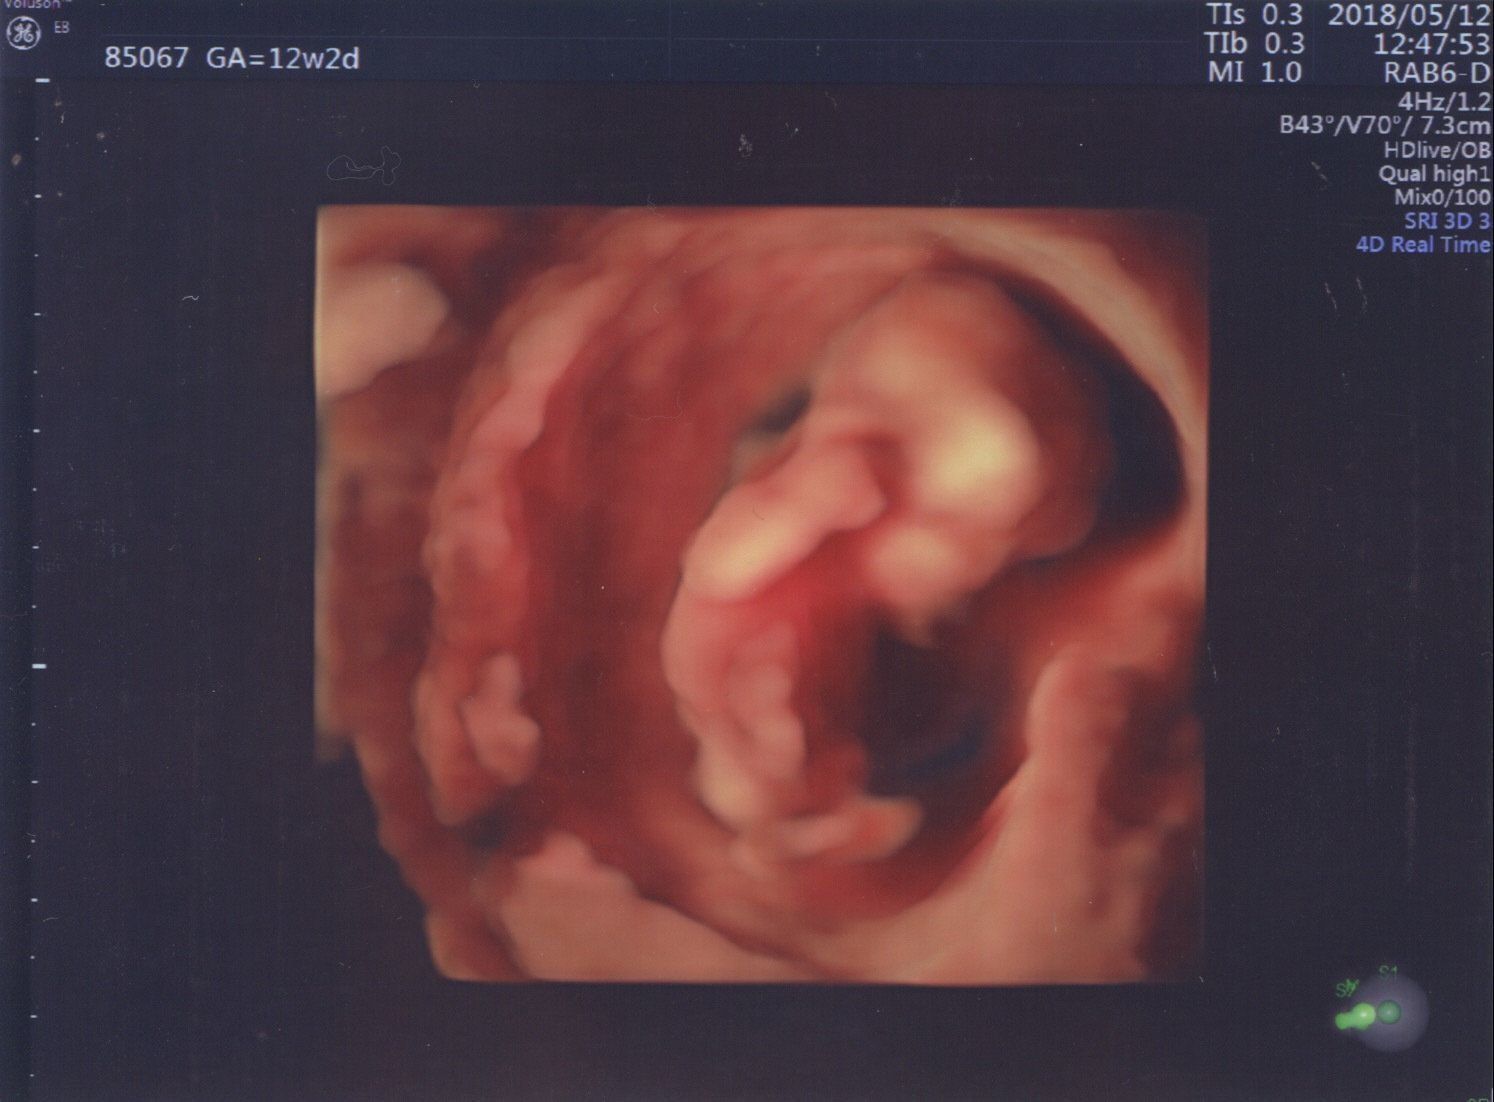

妊娠12週目 初めての腹部エコー

妊娠12週目で行った初めての腹部エコーは、夫と一緒におなかの中の赤ちゃんを見た初めての日となりました。

先生が4Dエコーを見せてくださり、思っていた以上にしっかりと赤ちゃんの姿が見えて驚きました。隣で一緒にエコーを見ていた夫も、心臓の音を聞き、息子の姿を目にして、実感が湧いたようでした。

右手を顔に当てている姿がとてもかわいかったです。このポーズは、1歳になった今でも寝ている時によくしています。